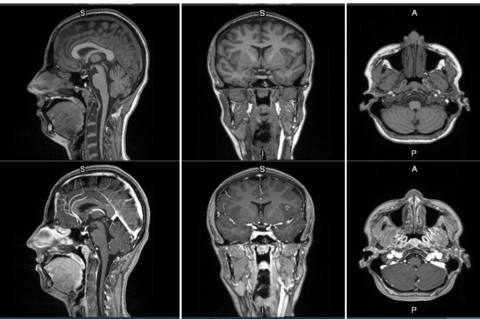

CHALFONT ST GILES, England--(BUSINESS WIRE)--GE HealthCare (Nasdaq: GEHC) today announced the first patient has been dosed in the international, multi-center Phase 2/3 LUMINA clinical trial of its manganese-based magnetic resonance imaging (MRI) contrast agent, mangaciclanol, at Mayo Clinic in Rochester, Minnesota. Mangaciclanol, if approved, could offer an alternative to – or even replace – gadolinium-based MRI contrast agents, the current standard of care. The investigational agent has been granted Fast Track designation by the U.S. Food and Drug Administration (FDA) for use in adults and pediatric patients aged 2 years and older with MRI to detect and visualize lesions with abnormal vascularity in the central nervous system and the body. FDA Fast Track designation expedites the review of new therapeutics and medical imaging agents that have the potential to address significant unmet patient needs.

MRI contrast agents enhance the visualization of abnormal structures or lesions during imaging procedures and help clinicians better distinguish between healthy and diseased tissue. Mangaciclanol is intended for general-purpose MR imaging and demonstrates comparable relaxivity (the ability to enhance signal intensity) to market-leading gadolinium-based agent, gadobutrol, with early clinical images suggesting similar diagnostic capability. Unlike gadolinium, which is a rare-earth metal, manganese is present in our food, and is an endogenous element, naturally occurring and autoregulated in the body. The macrocyclic ‘cage-like’ structure of mangaciclanol lessens the possibility of retention.

Phase 1 results for mangaciclanol showed the investigational agent was well tolerated in a first in human trial with no serious adverse events, no dose limiting toxicities, nor clinically relevant findings reported.